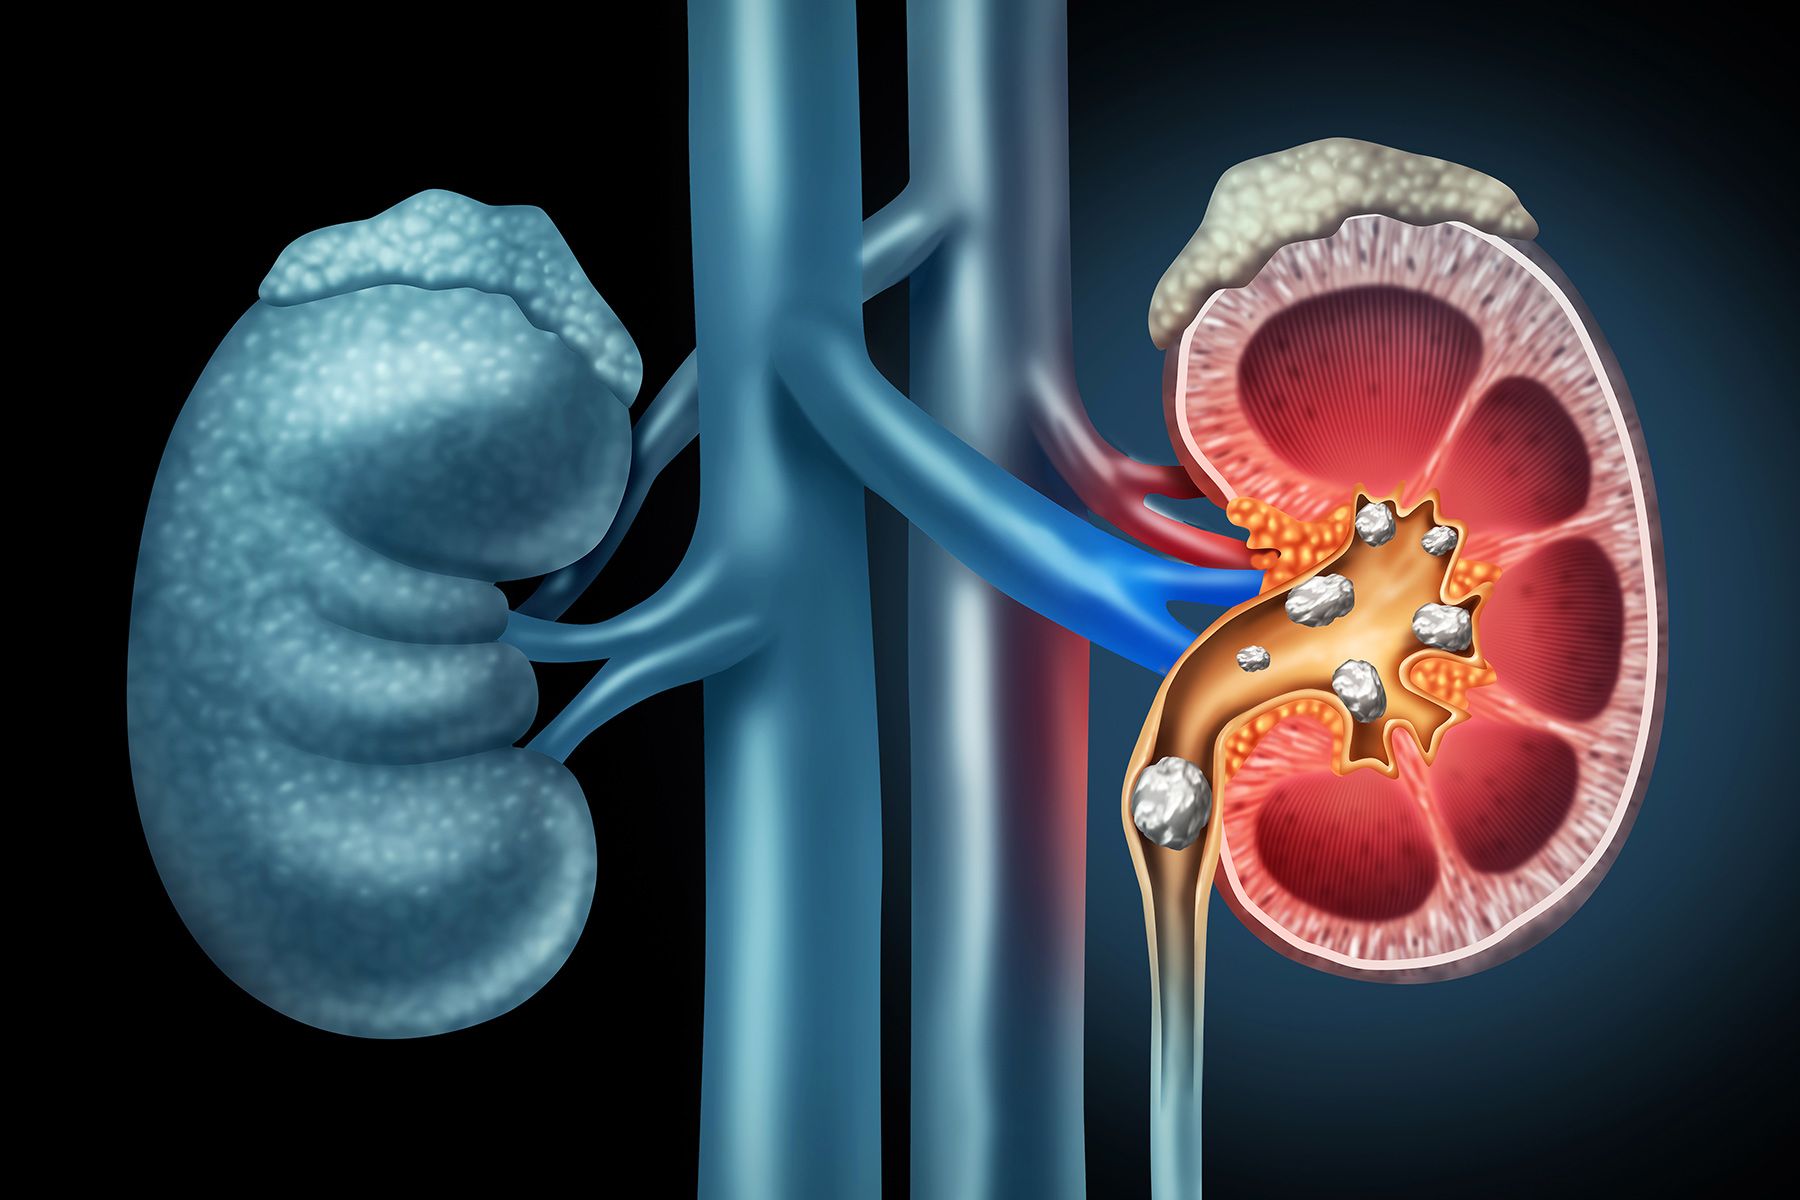

Urinary Stones (Kidney and Bladder)

Stones can cause pain, infections, or blood in the urine. Treatments include laser stone fragmentation (ureteroscopy), shockwave therapy (ESWL), and keyhole surgery (PCNL) for complex or larger stones. PCNL and ESWL would be referred to the NHS due to the specialised facilities required.